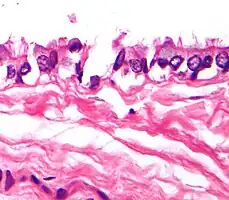

| Micrograph of a mediastinal bronchogenic cyst – H&E stain | |

Bronchogenic cysts are formed in the 6th week of gestation from an abnormal budding of the tracheal diverticulum. They are lined by respiratory type (ciliated) epithelium, which is characterized by cilia. Histologically these are also composed of cartilage, smooth muscle, fibrous tissue and mucous glands. These cysts originate from the ventral foregut that forms the respiratory system. These cysts are located close to the trachea or main stem bronchi. Rarely there is communication of the cyst with the tracheobronchial tree.

Very high magnification light micrograph showing the cilia of a bronchogenic cyst. H&E stain.